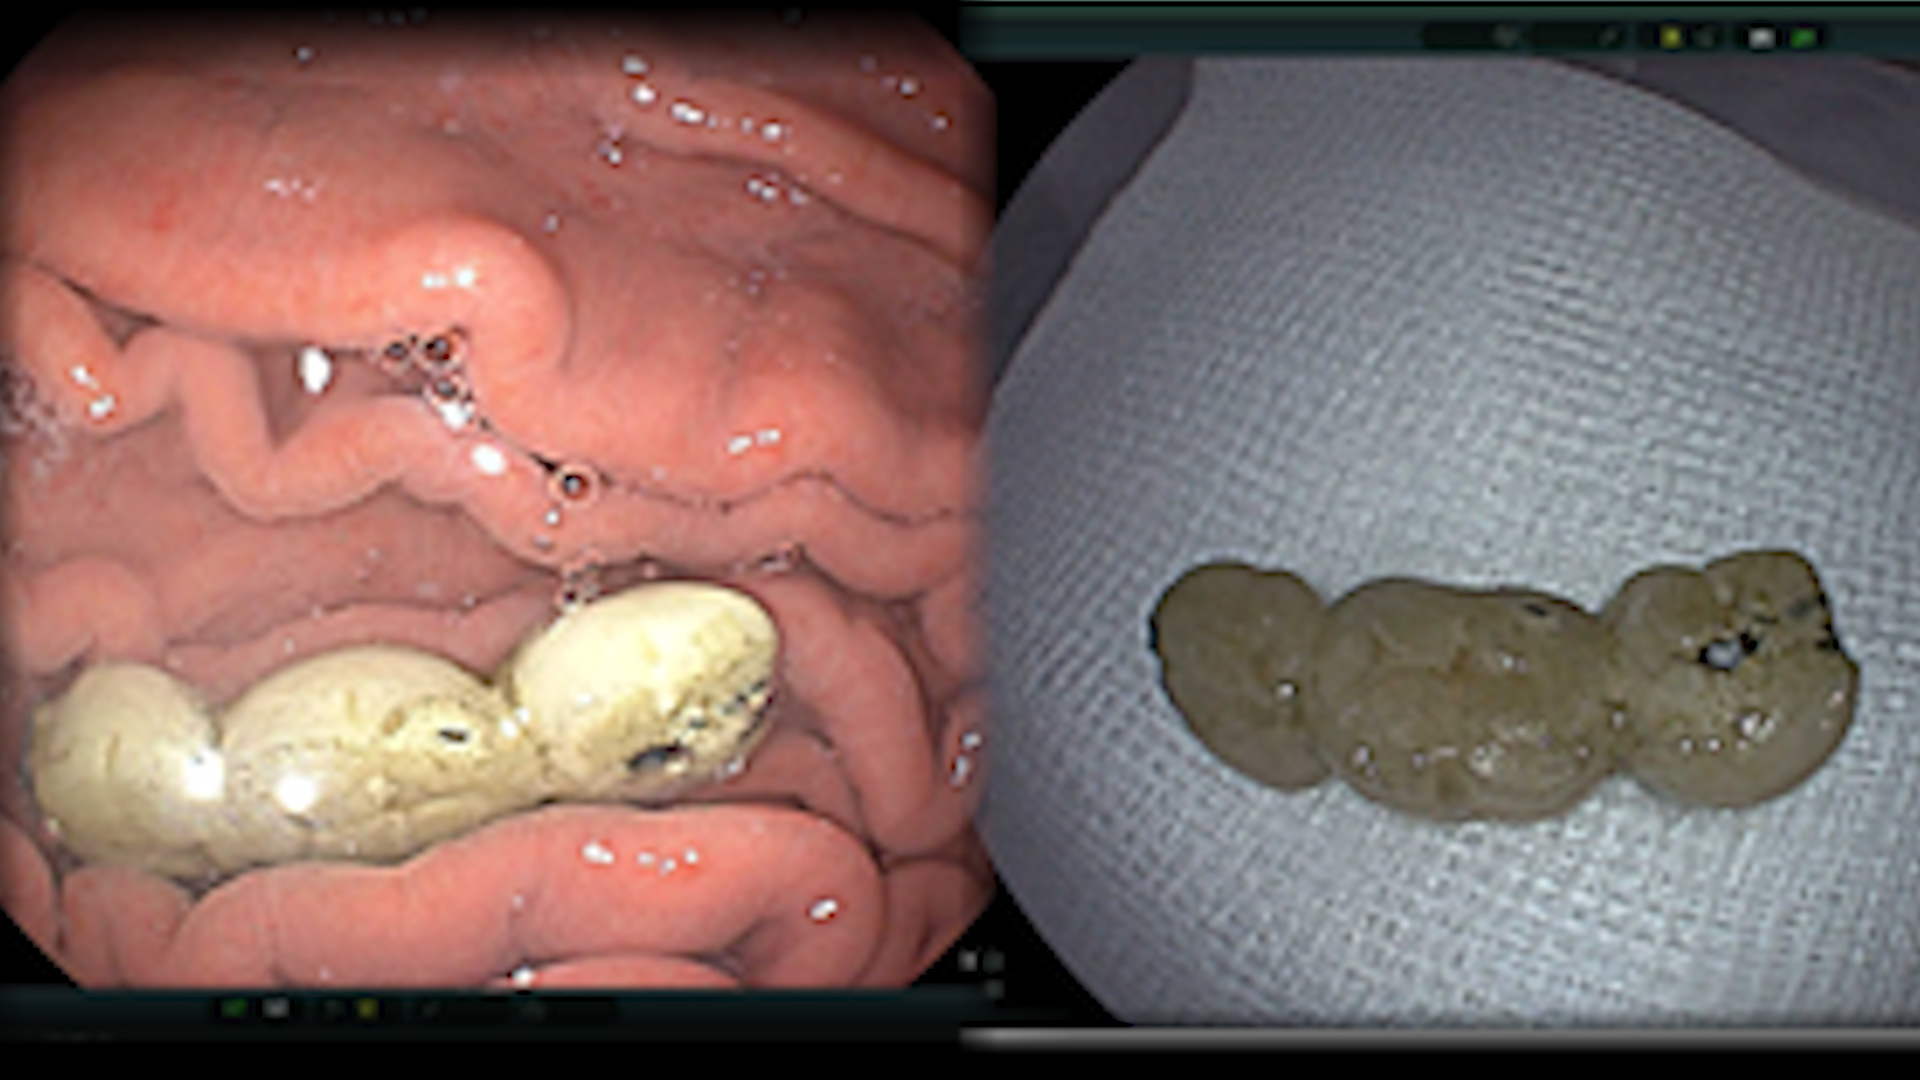

Trường hợp thứ hai là bệnh nhân nam 69 tuổi, đến khám bệnh vì nuốt cầu răng giả bị rơi ra trong quá trình ăn uống. Người bệnh đã được tiến hành nội soi phát hiện dị vật là cầu răng giả dài 4cm nằm trong dạ dày và nhanh chóng gắp ra ngoài an toàn.

| Cầu răng giả được lấy ra từ dạ dày bệnh nhân - Ảnh: Bệnh viện cung cấp |